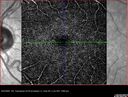

Peripapillary CNVM No Treatment

85 year old with peripapillary CNVM watched for many years.